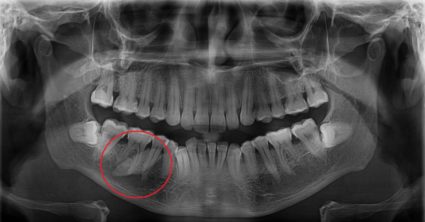

Celkovo odstránili niekoľko svalov, kostí, sliznicu ústnej dutiny a tkanivo pažeráka, ako aj slinnú časť a šesť zubov. Pri zákroku sa snažili čo najviac zachovať tvárové nervy.